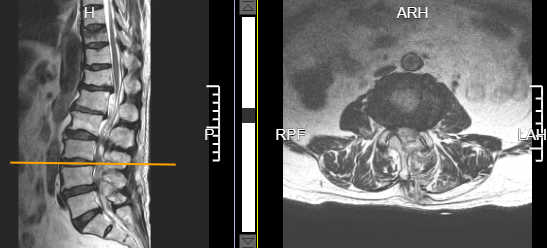

术前腰3/4椎间盘突出并椎管狭窄

术后腰3/4椎管减压后狭窄解除